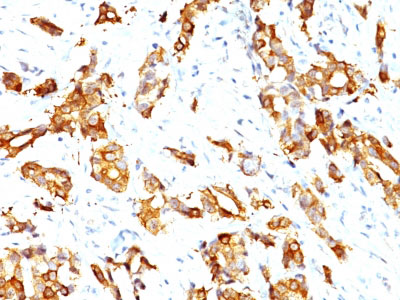

Formalin-fixed, paraffin-embedded human Breast Carcinoma stained with HSP27 Monoclonal Antibody (HSPB1/774)

Formalin-fixed, paraffin-embedded human Prostate Carcinoma stained with HSP27 Monoclonal Antibody (HSPB1/774) |